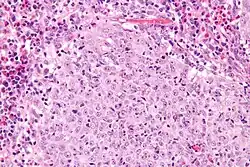

Micrograph of a glassy cell carcinoma of the cervix. H&E stain.

Glassy cell carcinoma of the cervix, also glassy cell carcinoma, is a rare aggressive malignant tumour of the uterine cervix.[1] The tumour gets its name from its microscopic appearance; its cytoplasm has a glass-like appearance.

Under the microscope, glassy cell carcinoma tumours are composed of cells with a glass-like cytoplasm, typically associated with an inflammatory infiltrate abundant in eosinophils and very mitotically active. PAS staining highlights the plasma membrane.[2]